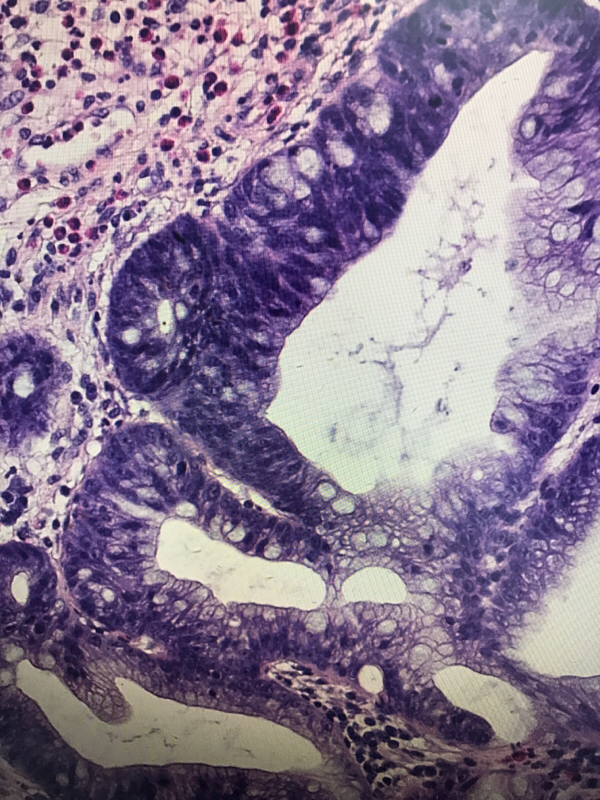

直肠息肉

一般病史

血便4天

灰红结节一枚,大小1✖️0.6✖️0.6cm,切面灰红,质软

管状腺瘤,低级别还是高级别?

幼年性息肉,灶性低级别

幼年性息肉?

幼年性息肉